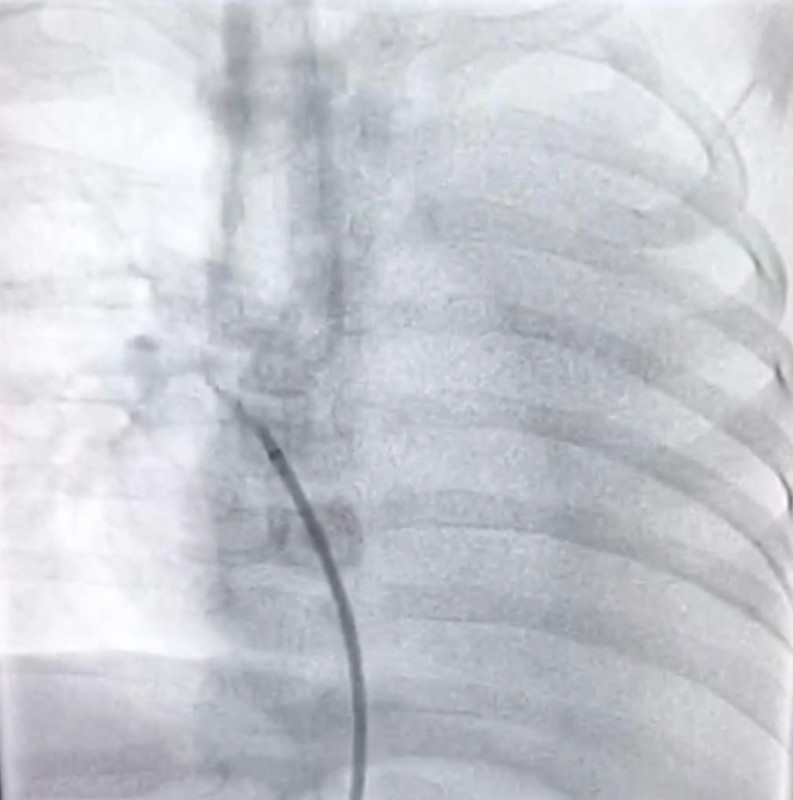

وأوضح مدير المركز الدكتور خالد أمين العطاس، أن الطفل أعطي أدوية لعلاج السوائل، ثم فحصه بجهاز أشعة القلب «إيكو»، واكتشف وجود شريان زايد يأتي من الشريان الأورطي النازل إلى الأُذين الأيسر في القلب، وهذه القناة تعتبر من القنوات النادرة جداً أن يكون مصب الدم من الأورطة مباشرة إلى الجهة اليسرى من القلب مباشرة، مشيراً إلى قسطرة تشخيصية عملت للطفل لمحاولة إقفال القناة بجهاز خاص وتكللت العملية بالنجاح.

أثناء إجراء العملية.